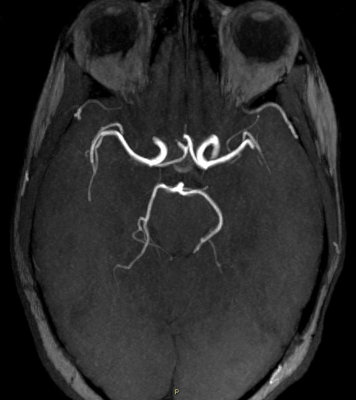

De façon physiologique, les artères communicantes postérieures ne sont pas très larges, y'a vraiment très peu de sang qui y passe (comme tu peux le voir sur ces deux angiographies) :